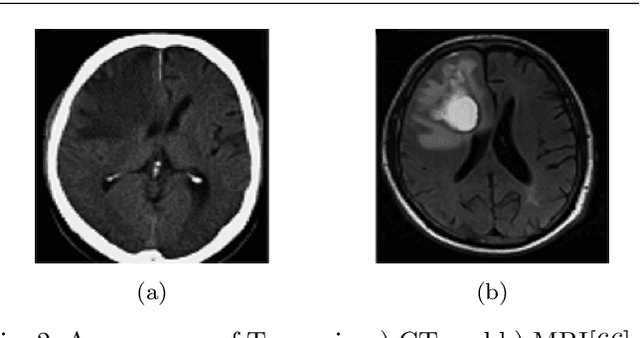

Abstract:Glioma is the most deadly brain tumor with high mortality. Treatment planning by human experts depends on the proper diagnosis of physical symptoms along with Magnetic Resonance(MR) image analysis. Highly variability of a brain tumor in terms of size, shape, location, and a high volume of MR images makes the analysis time-consuming. Automatic segmentation methods achieve a reduction in time with excellent reproducible results. The article aims to survey the advancement of automated methods for Glioma brain tumor segmentation. It is also essential to make an objective evaluation of various models based on the benchmark. Therefore, the 2012 - 2019 BraTS challenges database evaluates state-of-the-art methods. The complexity of tasks under the challenge has grown from segmentation (Task1) to overall survival prediction (Task 2) to uncertainty prediction for classification (Task 3). The paper covers the complete gamut of brain tumor segmentation using handcrafted features to deep neural network models for Task 1. The aim is to showcase a complete change of trends in automated brain tumor models. The paper also covers end to end joint models involving brain tumor segmentation and overall survival prediction. All the methods are probed, and parameters that affect performance are tabulated and analyzed.

Abstract:Glioblastoma Multiforme is a very aggressive type of brain tumor. Due to spatial and temporal intra-tissue inhomogeneity, location and the extent of the cancer tissue, it is difficult to detect and dissect the tumor regions. In this paper, we propose survival prognosis models using four regressors operating on handcrafted image-based and radiomics features. We hypothesize that the radiomics shape features have the highest correlation with survival prediction. The proposed approaches were assessed on the Brain Tumor Segmentation (BraTS-2020) challenge dataset. The highest accuracy of image features with random forest regressor approach was 51.5\% for the training and 51.7\% for the validation dataset. The gradient boosting regressor with shape features gave an accuracy of 91.5\% and 62.1\% on training and validation datasets respectively. It is better than the BraTS 2020 survival prediction challenge winners on the training and validation datasets. Our work shows that handcrafted features exhibit a strong correlation with survival prediction. The consensus based regressor with gradient boosting and radiomics shape features is the best combination for survival prediction.

Abstract:Glioma, the malignant brain tumor, requires immediate treatment to improve the survival of patients. Gliomas heterogeneous nature makes the segmentation difficult, especially for sub-regions like necrosis, enhancing tumor, non-enhancing tumor, and Edema. Deep neural networks like full convolution neural networks and ensemble of fully convolution neural networks are successful for Glioma segmentation. The paper demonstrates the use of a 3D fully convolution neural network with a three layer encoder decoder approach for layer arrangement. The encoder blocks include the dense modules, and decoder blocks include convolution modules. The input to the network is 3D patches. The loss function combines dice loss and focal loss functions. The validation set dice score of the network is 0.74, 0.88, and 0.73 for enhancing tumor, whole tumor, and tumor core, respectively. The Random Forest Regressor uses shape, volumetric, and age features extracted from ground truth for overall survival prediction. The regressor achieves an accuracy of 44.8% on the validation set.